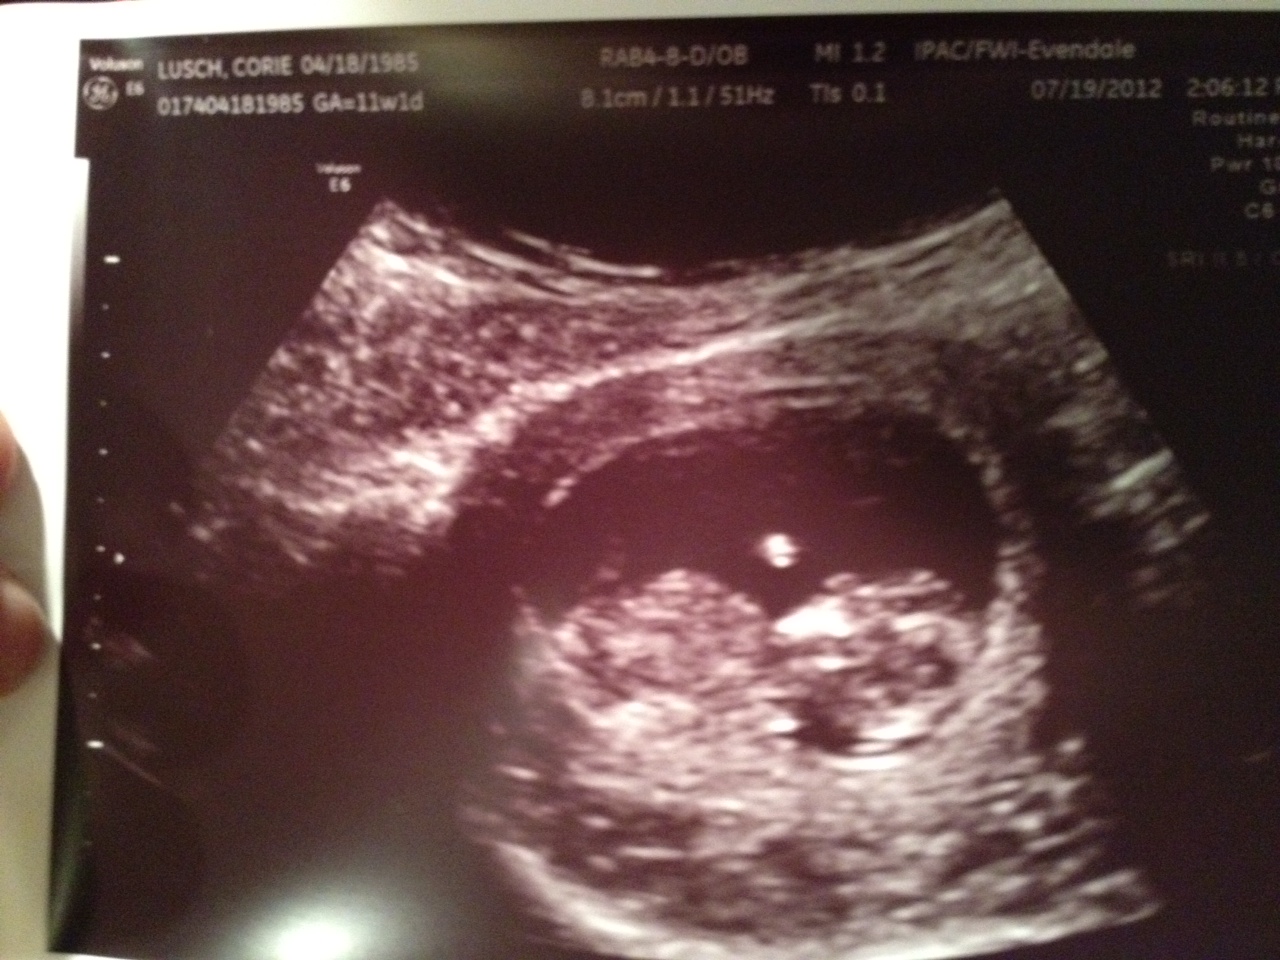

We had our first ultra sound last week and were given four beautiful pictures. I am truly amazed that babies form so quickly and everything that they need is there within the first trimester. It is beyond my understanding but that is why we have such a wonderful and intelligent creator. Perfectly designing every aspect of the way humans grow but also every other creature throughout this entire world. WOW!

This lil one kept squirming and moving all over so we really didn't get any great pictures but I wanted to share them with you as they are really cool.

This one shows the heartbeat at the bottom. The heart rate was 175 beats. Brock and I were shocked to hear that but the tech informed us that is was completely normal and healthy. So much faster than a fully grown adult.